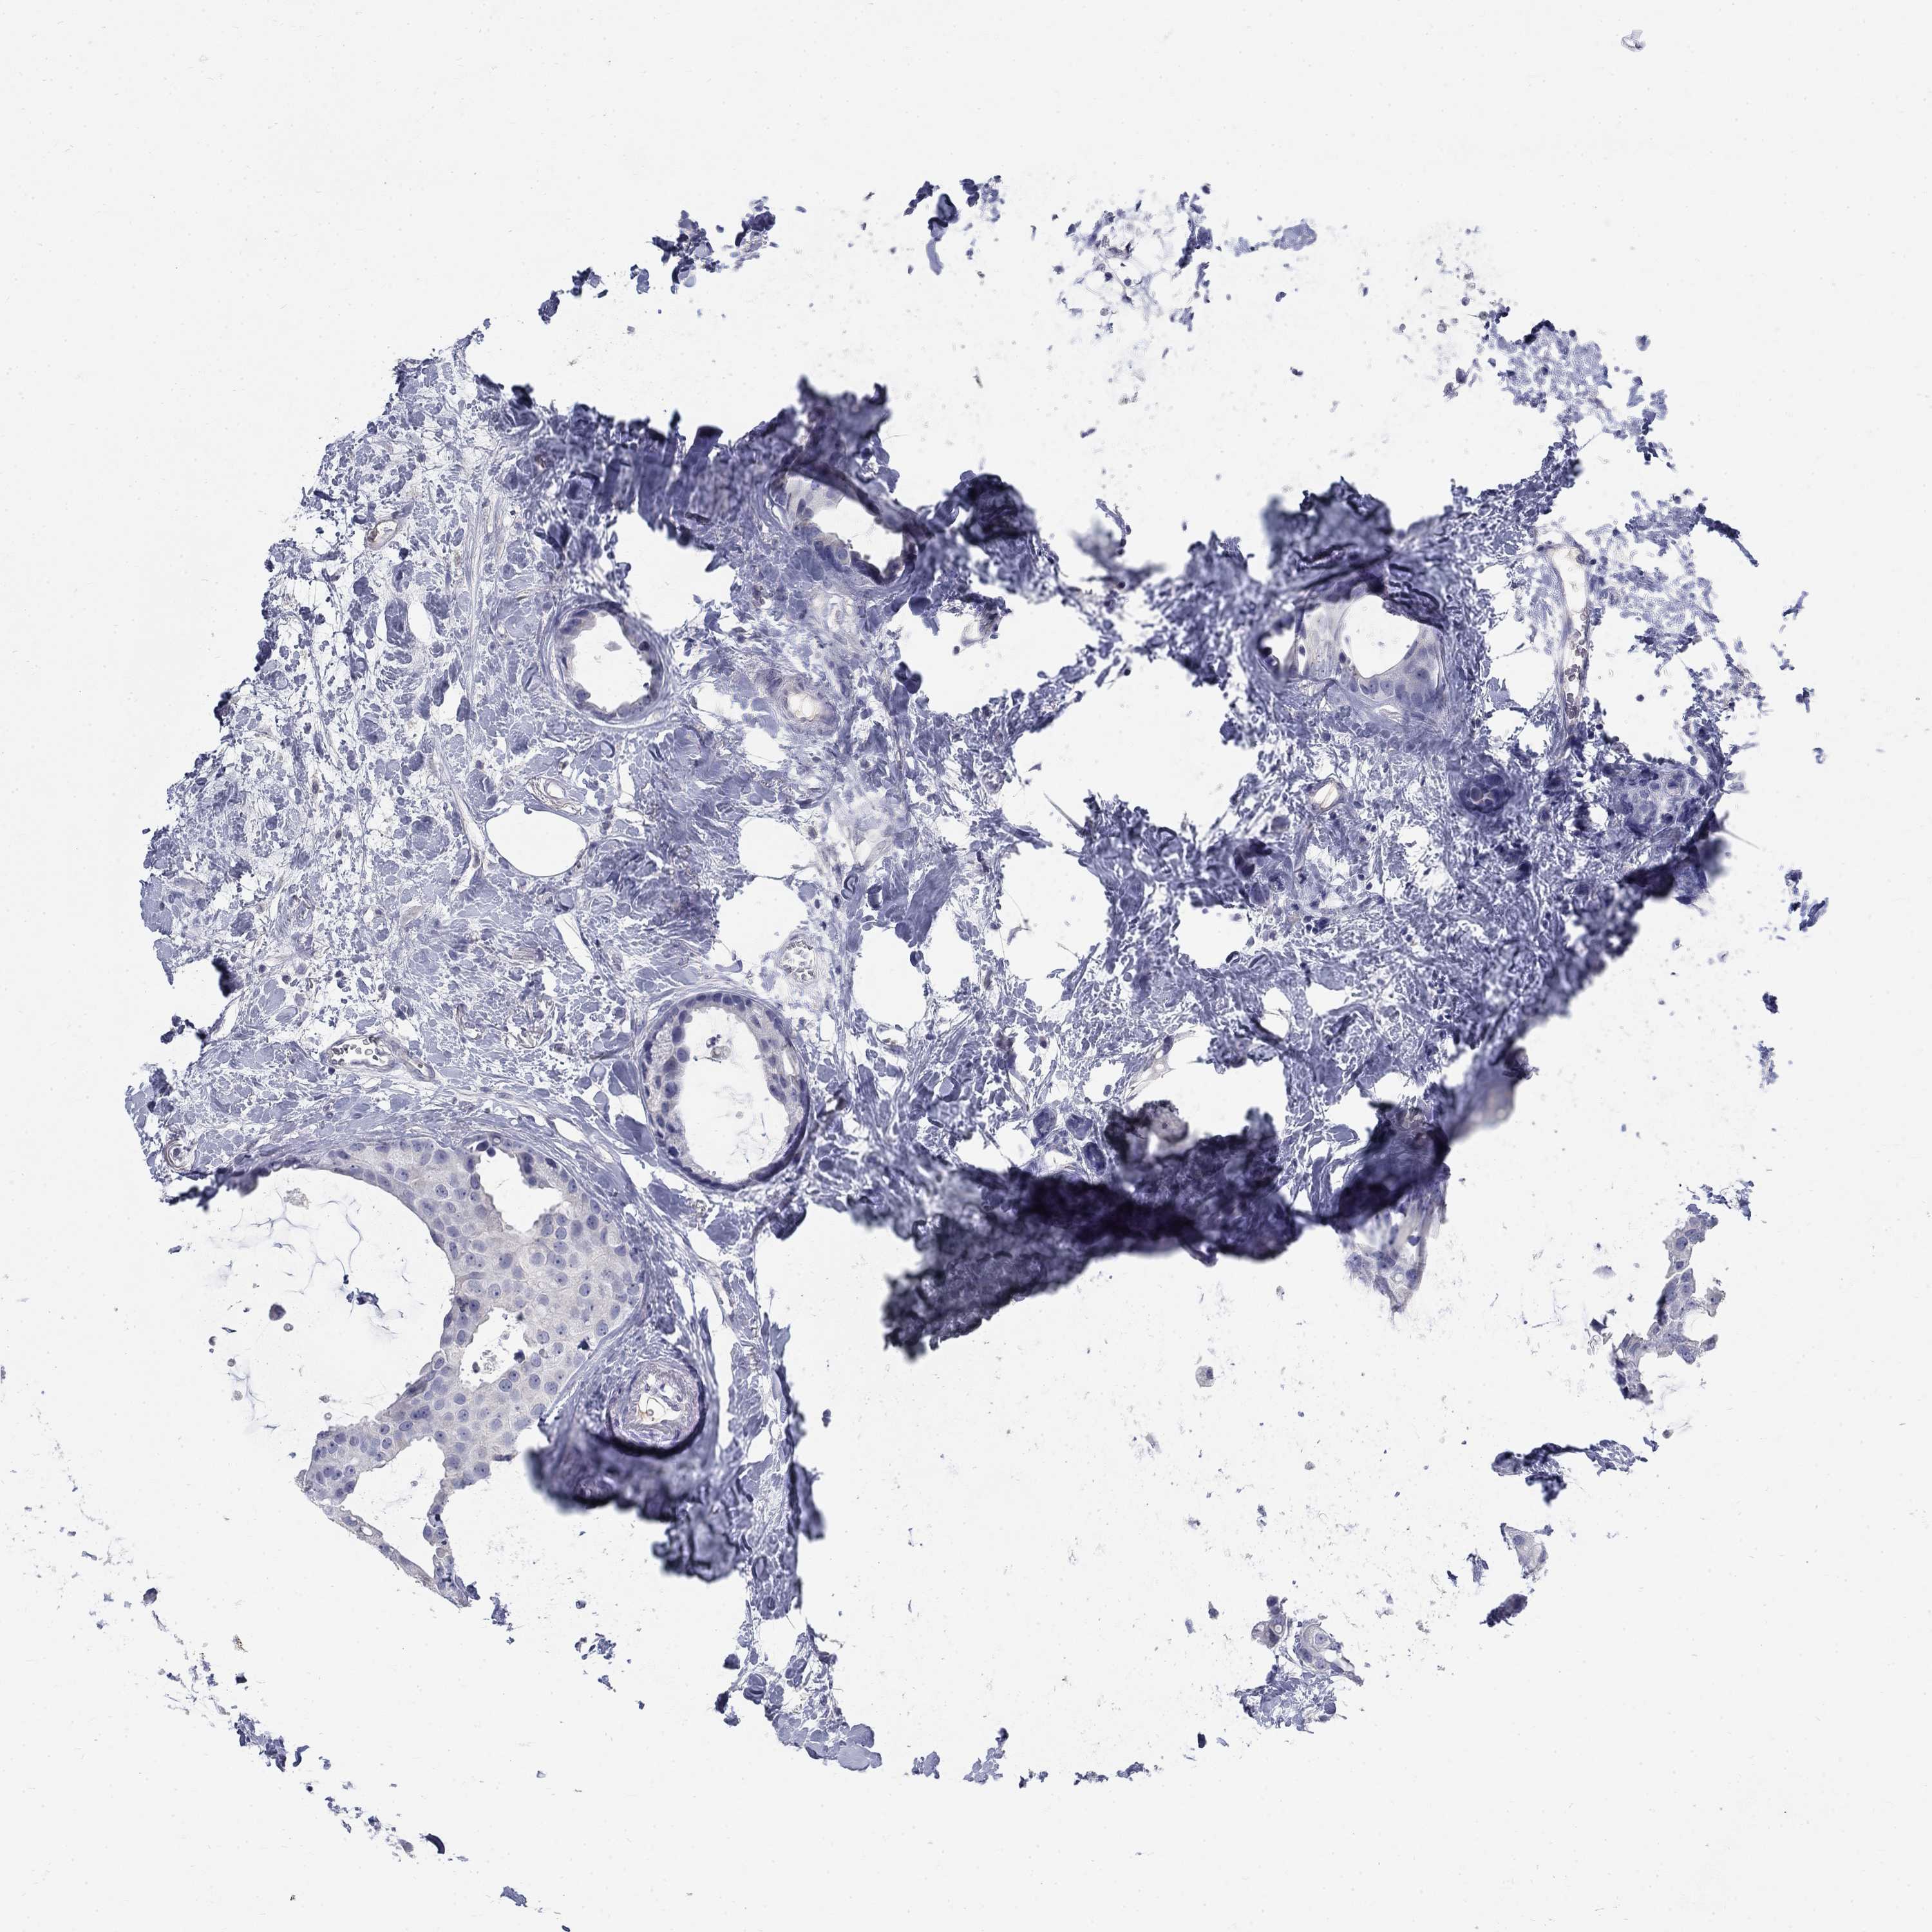

CANCER BREAST CANCER Show tissue menu

Breast cancer

Human cancer